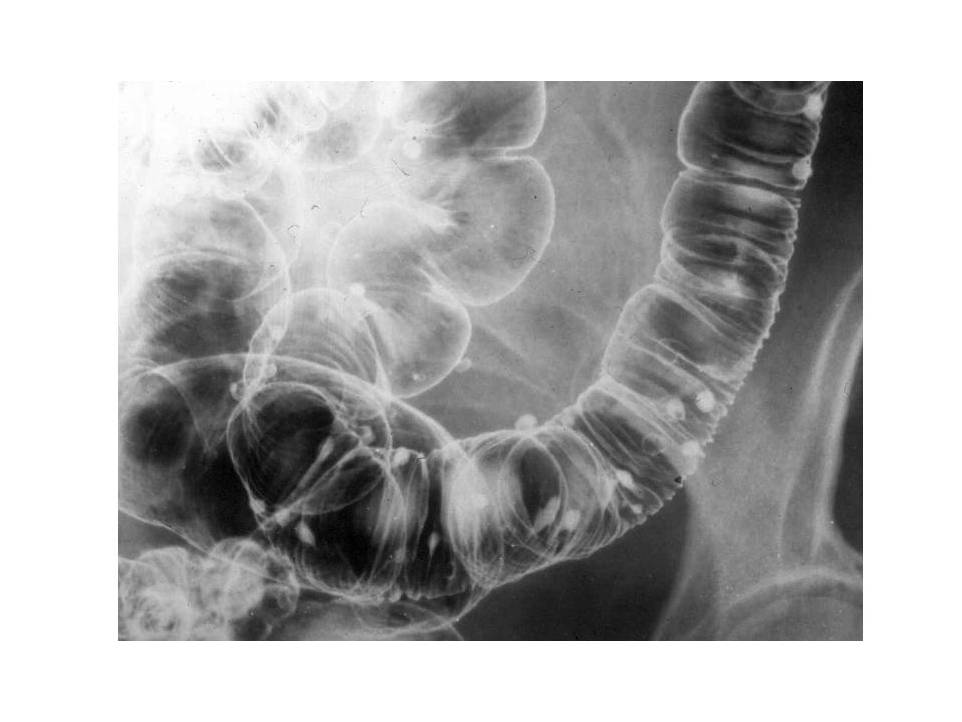

Image

Fig.22. Crohn’s disease

Radiographic findings: Most frequently luminal narrowing of the terminal ileum is detected. The wall is thickened, intramural and inter-intestinal fistulas may develop. The abdominal plain film is not suitable for identification of abdominal abscesses.

Double-contrast irrigoscopy.

Fig.23.: Radiographic image: multiple, round filling defects are seen on the sigma and on the descending colon.

Fig.24.: Double-contrast irrigoscopy